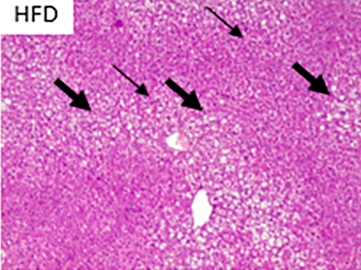

Fotografías a cortes histológicos de hígado, después de 12 semanas, parte de ensayo preclínico: CD: dieta control; HFD: dieta alta en grasa; A1: dieta alta en grasa + concentrado Omega-3 pescado; y A4: dieta alta en grasa + lípidos terapéuticos Nutri-Omics. Flechas muestran los distintos niveles de gravedad de los focos de esteatosis macro y micro vesicular después de ser sometidos a una dieta alta en grasa.